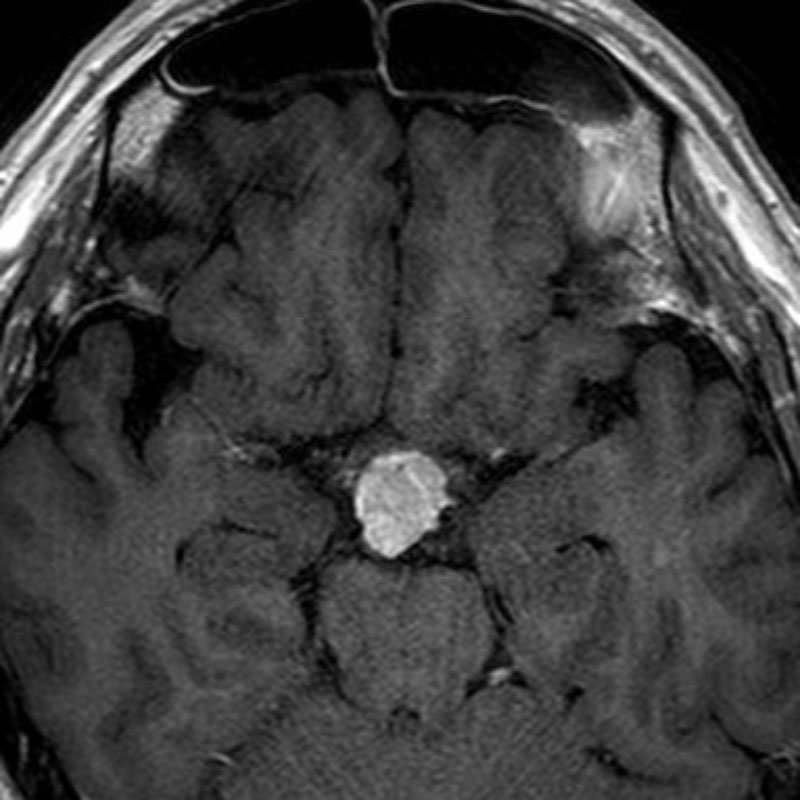

528

'24年5月

40代

脳室内腫瘍

頭蓋内腫瘍摘出術

No.’24_30 手術前1

No.’24_30 手術前2